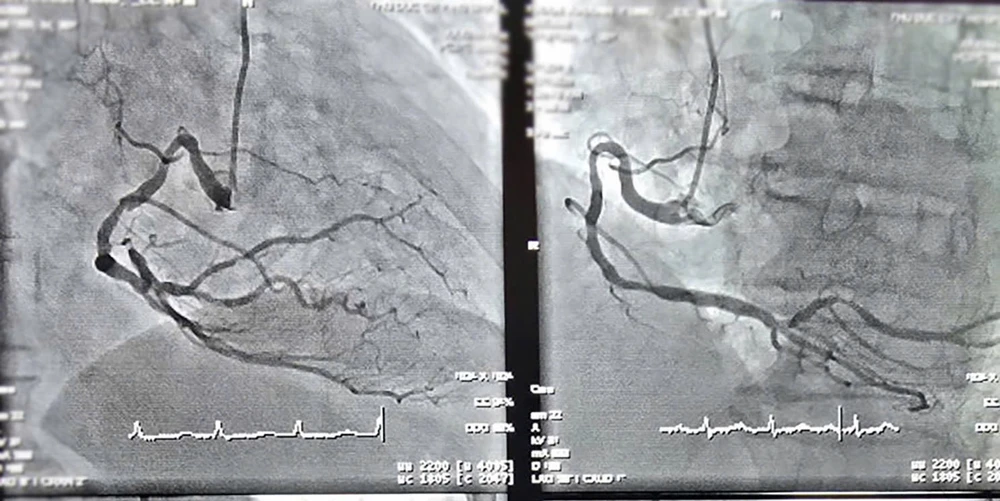

Hình ảnh chụp mạch vành của cụ ông 90 tuổi trước phẫu thuật. Ảnh: BVCC

Qua thăm khám, các bác sĩ xác định bệnh nhân bị nhồi máu cơ tim cấp, bán tắc động mạch liên thất trước (LAD) và hẹp nặng ba nhánh mạch vành.

Tình trạng bệnh phức tạp hơn do người bệnh có nhiều bệnh nền như tăng huyết áp, bệnh thận mạn giai đoạn 3, bệnh phổi tắc nghẽn mạn tính (COPD) và tiền sử hút thuốc lá.